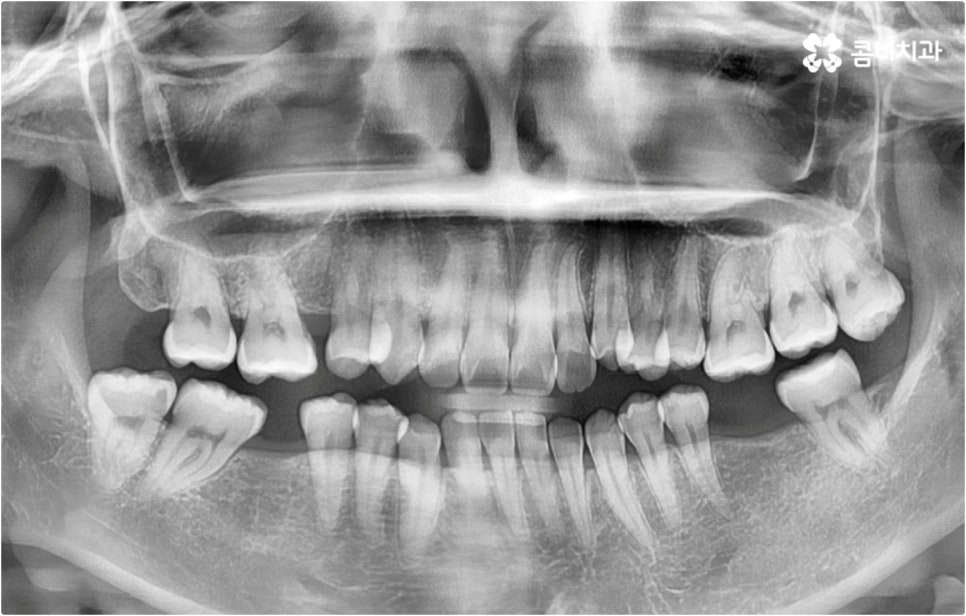

그러나 누구나 부분 교정이 가능한 것은 아니며 실제로 검진을 해 보면 부분 교정 보다 전체 교정이 필요하다고 판단되는 경우가 많아 내심 실망하실 수도 있는데요. 이때 만약 무리해서 환자분들 자신이 원하는 대로 부분 교정을 고집하게 되면 치아 이동 결과가 만족스러운 수준까지 이루어지기 어렵고 부정교합의 원인에 대한 구조적인 개선이 미흡하여 문제가 재발하기 쉬우니 노하우가 풍부한 담당 의료진의 판단을 심사숙고 해 보실 필요가 있어요. 무작정 따라야 한다는 것이 아니라 숙련된 의료진이 환자분들 치아의 위치와 각도 및 교합, 그리고 구조적인 원인 등을 세심하게 검진하고 꼼꼼하게 체크하여 삐뚤어진 치열을 보다 효과적으로 바로잡는데 전체 교정 치료가 필요한 상황이라고 결론 내린 것이니 만큼 그 필요성에 대해 스스로 이해할 수 있도록 충분한 상담을 받아 보시길 권유드리는 거예요.

이때 현재 상황을 정밀하게 보여주는 3D CT, 미래 결과를 예측해서 보여주는 모르페우스와 같은 디지털 장비를 통해 전체 플랜을 자세하게 설명해 주고 중간 과정 역시 꼼꼼하게 브리핑해 주는 의료진과 함께 교정 치료를 진행한다면 조금은 길고 힘들게 느껴질 수 있는 전체 교정 과정에 보다 적극적이고 긍정적인 마음으로 임할 수 있을 거예요. 또한 앞서 말씀드린 것처럼 불편함을 줄여줄 수 있는 다양한 교정 장치와 방법 등이 있으니 가능한 선택지 내에서 자신의 상황에 최적화된 장치를 이용해 보시면 여러모로 도움을 받으실 수 있습니다.

이와 같이 치아설측교정 과 콤비교정은 브라켓을 치아 안쪽으로 붙여서 치료하는 방식이기 때문에 굉장히 고난도의 복잡한 교정 치료라고 할 수 있습니다. 교정에 대한 높은 이해도와 해부학적으로 뛰어난 노하우, 풍부한 경험을 통해 축적한 세심한 기술력을 갖추고 있는 의료진에게 치료를 맡기는 것이 중요하며 정밀 디지털 검진 장비를 통한 정확한 검사 결과를 바탕으로 무리하지 않게 진행하실 필요가 있어요. 또한 양치질을 할 때 음식물 제거가 쉽지 않으므로 환자분들 본인이 평상시 신경써서 닦아주시는 것은 물론 꼼꼼한 케어시스템을 통해 주기적으로 관리해 주는 치과에서 교정 치료 및 사후 유지 관리까지 철저하게 받아보시길 권유드리고 있습니다.